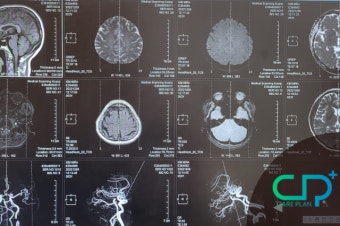

**쿠루병(Kuru)**은 아주 희귀한 신경계 질환입니다. 뇌가 서서히 망가져서 결국 사망에 이르게 되죠. 한때 파푸아뉴기니의 특정 부족에서만 발생했기 때문에, 지역성 질환으로 알려졌습니다.

쿠루병의 원인은 **프리온(prion)**이라는 아주 특이한 존재였습니다. 프리온은 살아있는 생명체도 아니고, 유전자도 없는 비정상 단백질이에요.

이 단백질은 마치 구겨진 종이가 옆 종이까지 구겨버리는 것처럼, 정상 단백질을 망가뜨리며 퍼집니다. 바이러스보다 더 단순하지만, 그 파괴력은 훨씬 치명적이었죠.